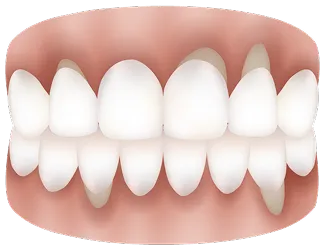

歯肉退縮とは

健康な歯肉

歯肉退縮

歯肉退縮は、歯を支える歯ぐきが徐々に減って歯が長く見える状態です。